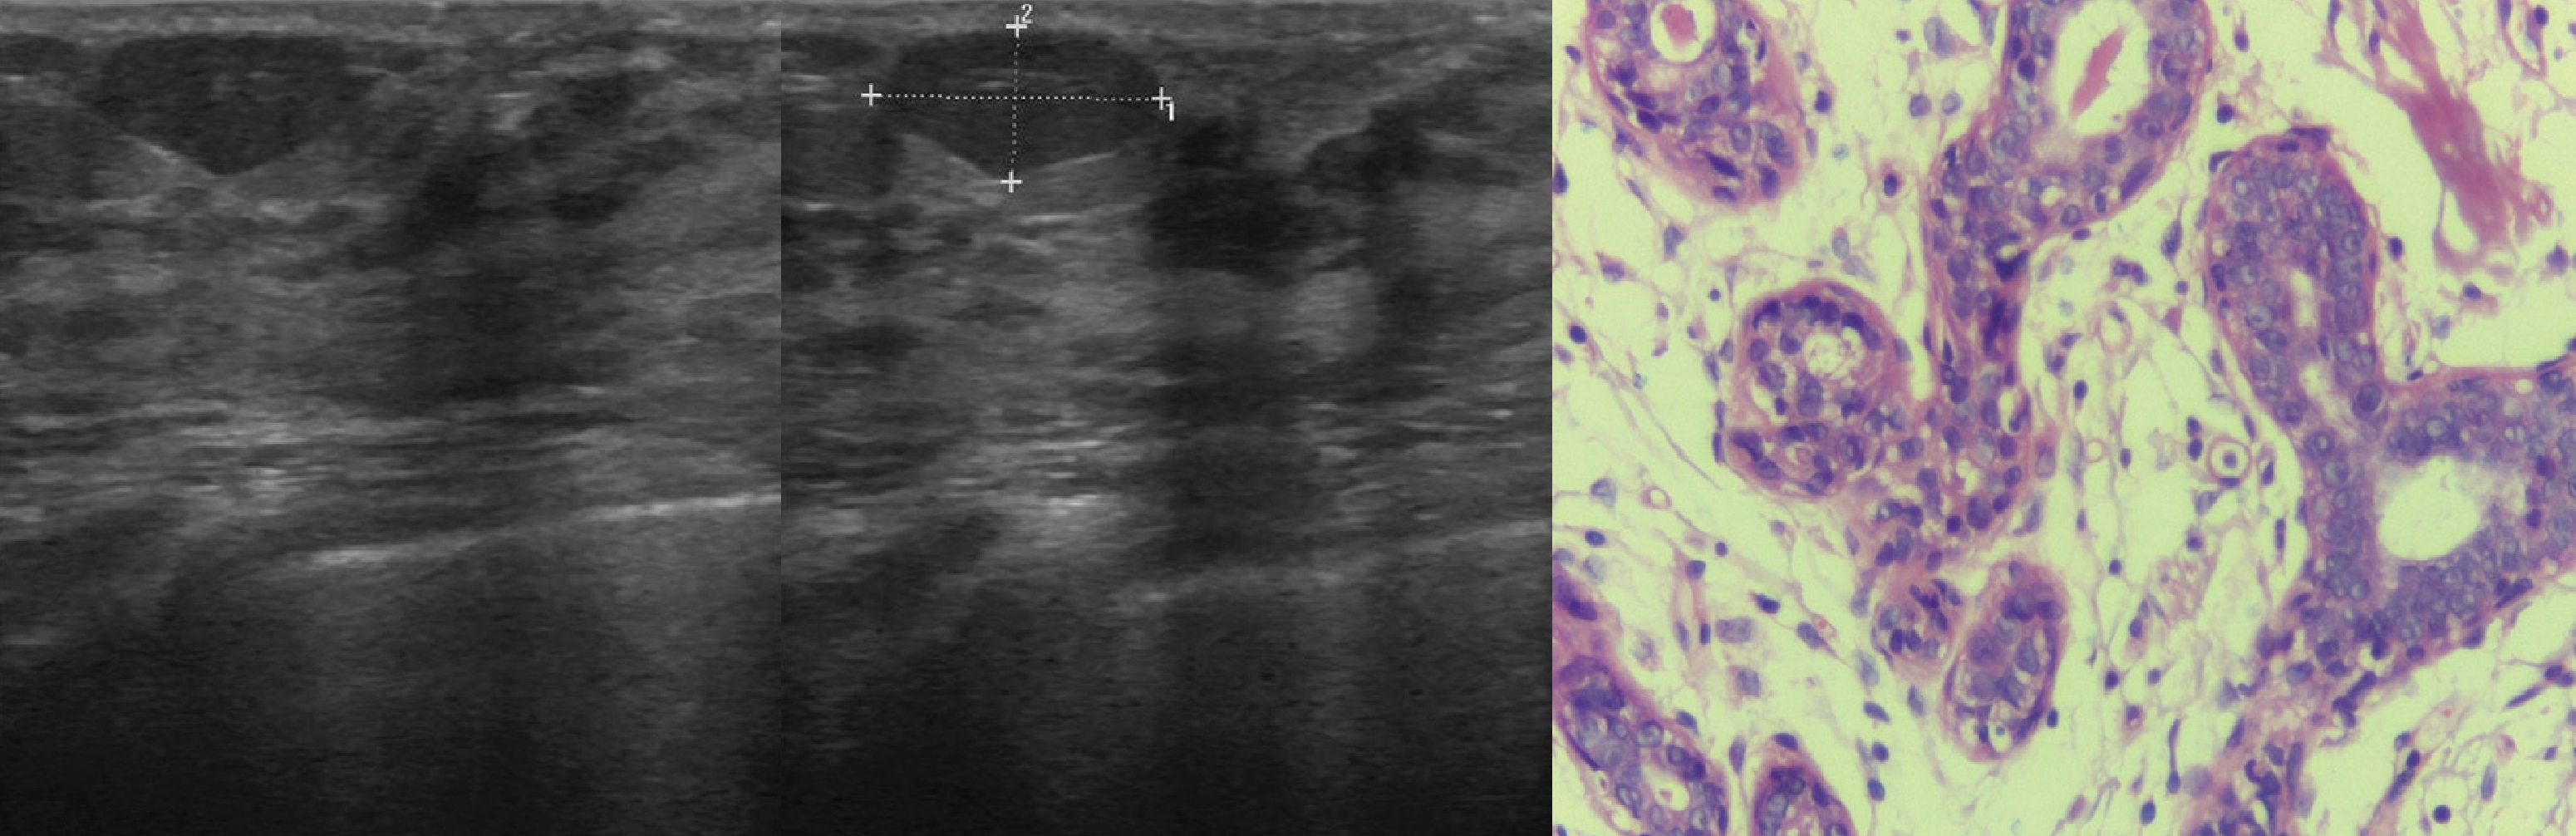

Микрогландулярный аденоз

Маммография и ее роль в диагностике фиброаденомы молочной железы

Маммография - это рентгенологическое исследование молочных желез. Оно позволяет выявить различные изменения в тканях, включая фиброаденому. На маммограммах можно увидеть структурные особенности опухоли и отследить ее динамику во времени.